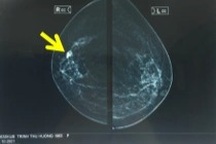

Dấu hiệu ung thư vú giai đoạn cuối

(Dân trí) - Ung thư vú giai đoạn cuối không thể chữa khỏi. Dấu hiệu của bệnh tùy thuộc vào vị trí khối u di căn đến là ở xương, phổi, gan hay não.

Ung thư vú giai đoạn 4 xảy ra khi ung thư di căn đến các cơ quan, mô hoặc hạch bạch huyết ở xa. Các chuyên gia chăm sóc sức khỏe cũng có thể gọi ung thư vú giai đoạn 4 là ung thư giai đoạn cuối, ung thư vú thứ phát hoặc ung thư vú di căn.